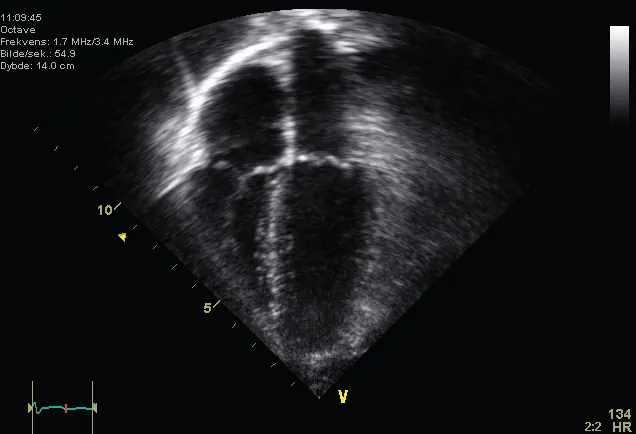

An echocardiogram (ECG) is an ultrasound of the heart that is used to determine if the heart valves and muscles are working correctly. In this photo, all four chambers of the heart can be seen.

This is an ultrasound picture of a normal heart showing all 4 chambers.

Figure 31.15 (credit: Kjetil Lenes, Wikimedia Commons)